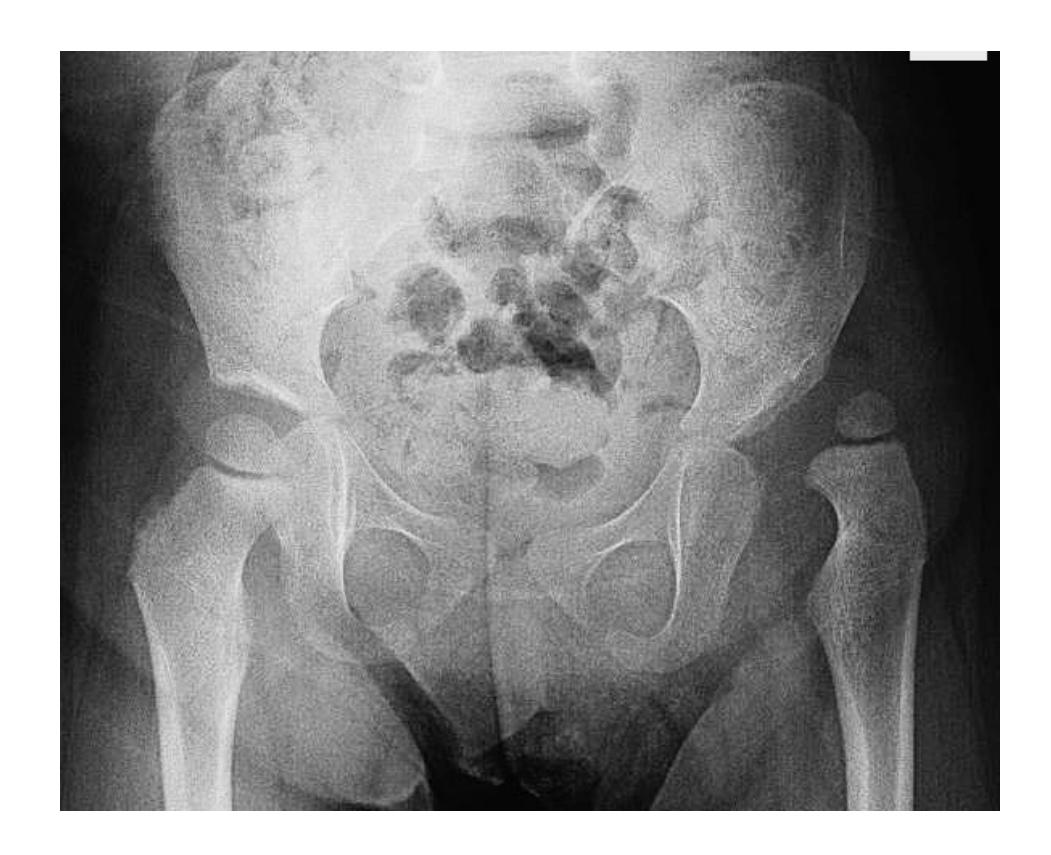

Give 2 abnormalities in this X-ray?

- Fracture of pubic bones

- Disrupted sacroiliac joint on the same side

Give first 2 measurements you need for saving life?

- ATLAS protocol (ABC)

- IV fluid administration

- IV analgesia

- Pelvic sheet application